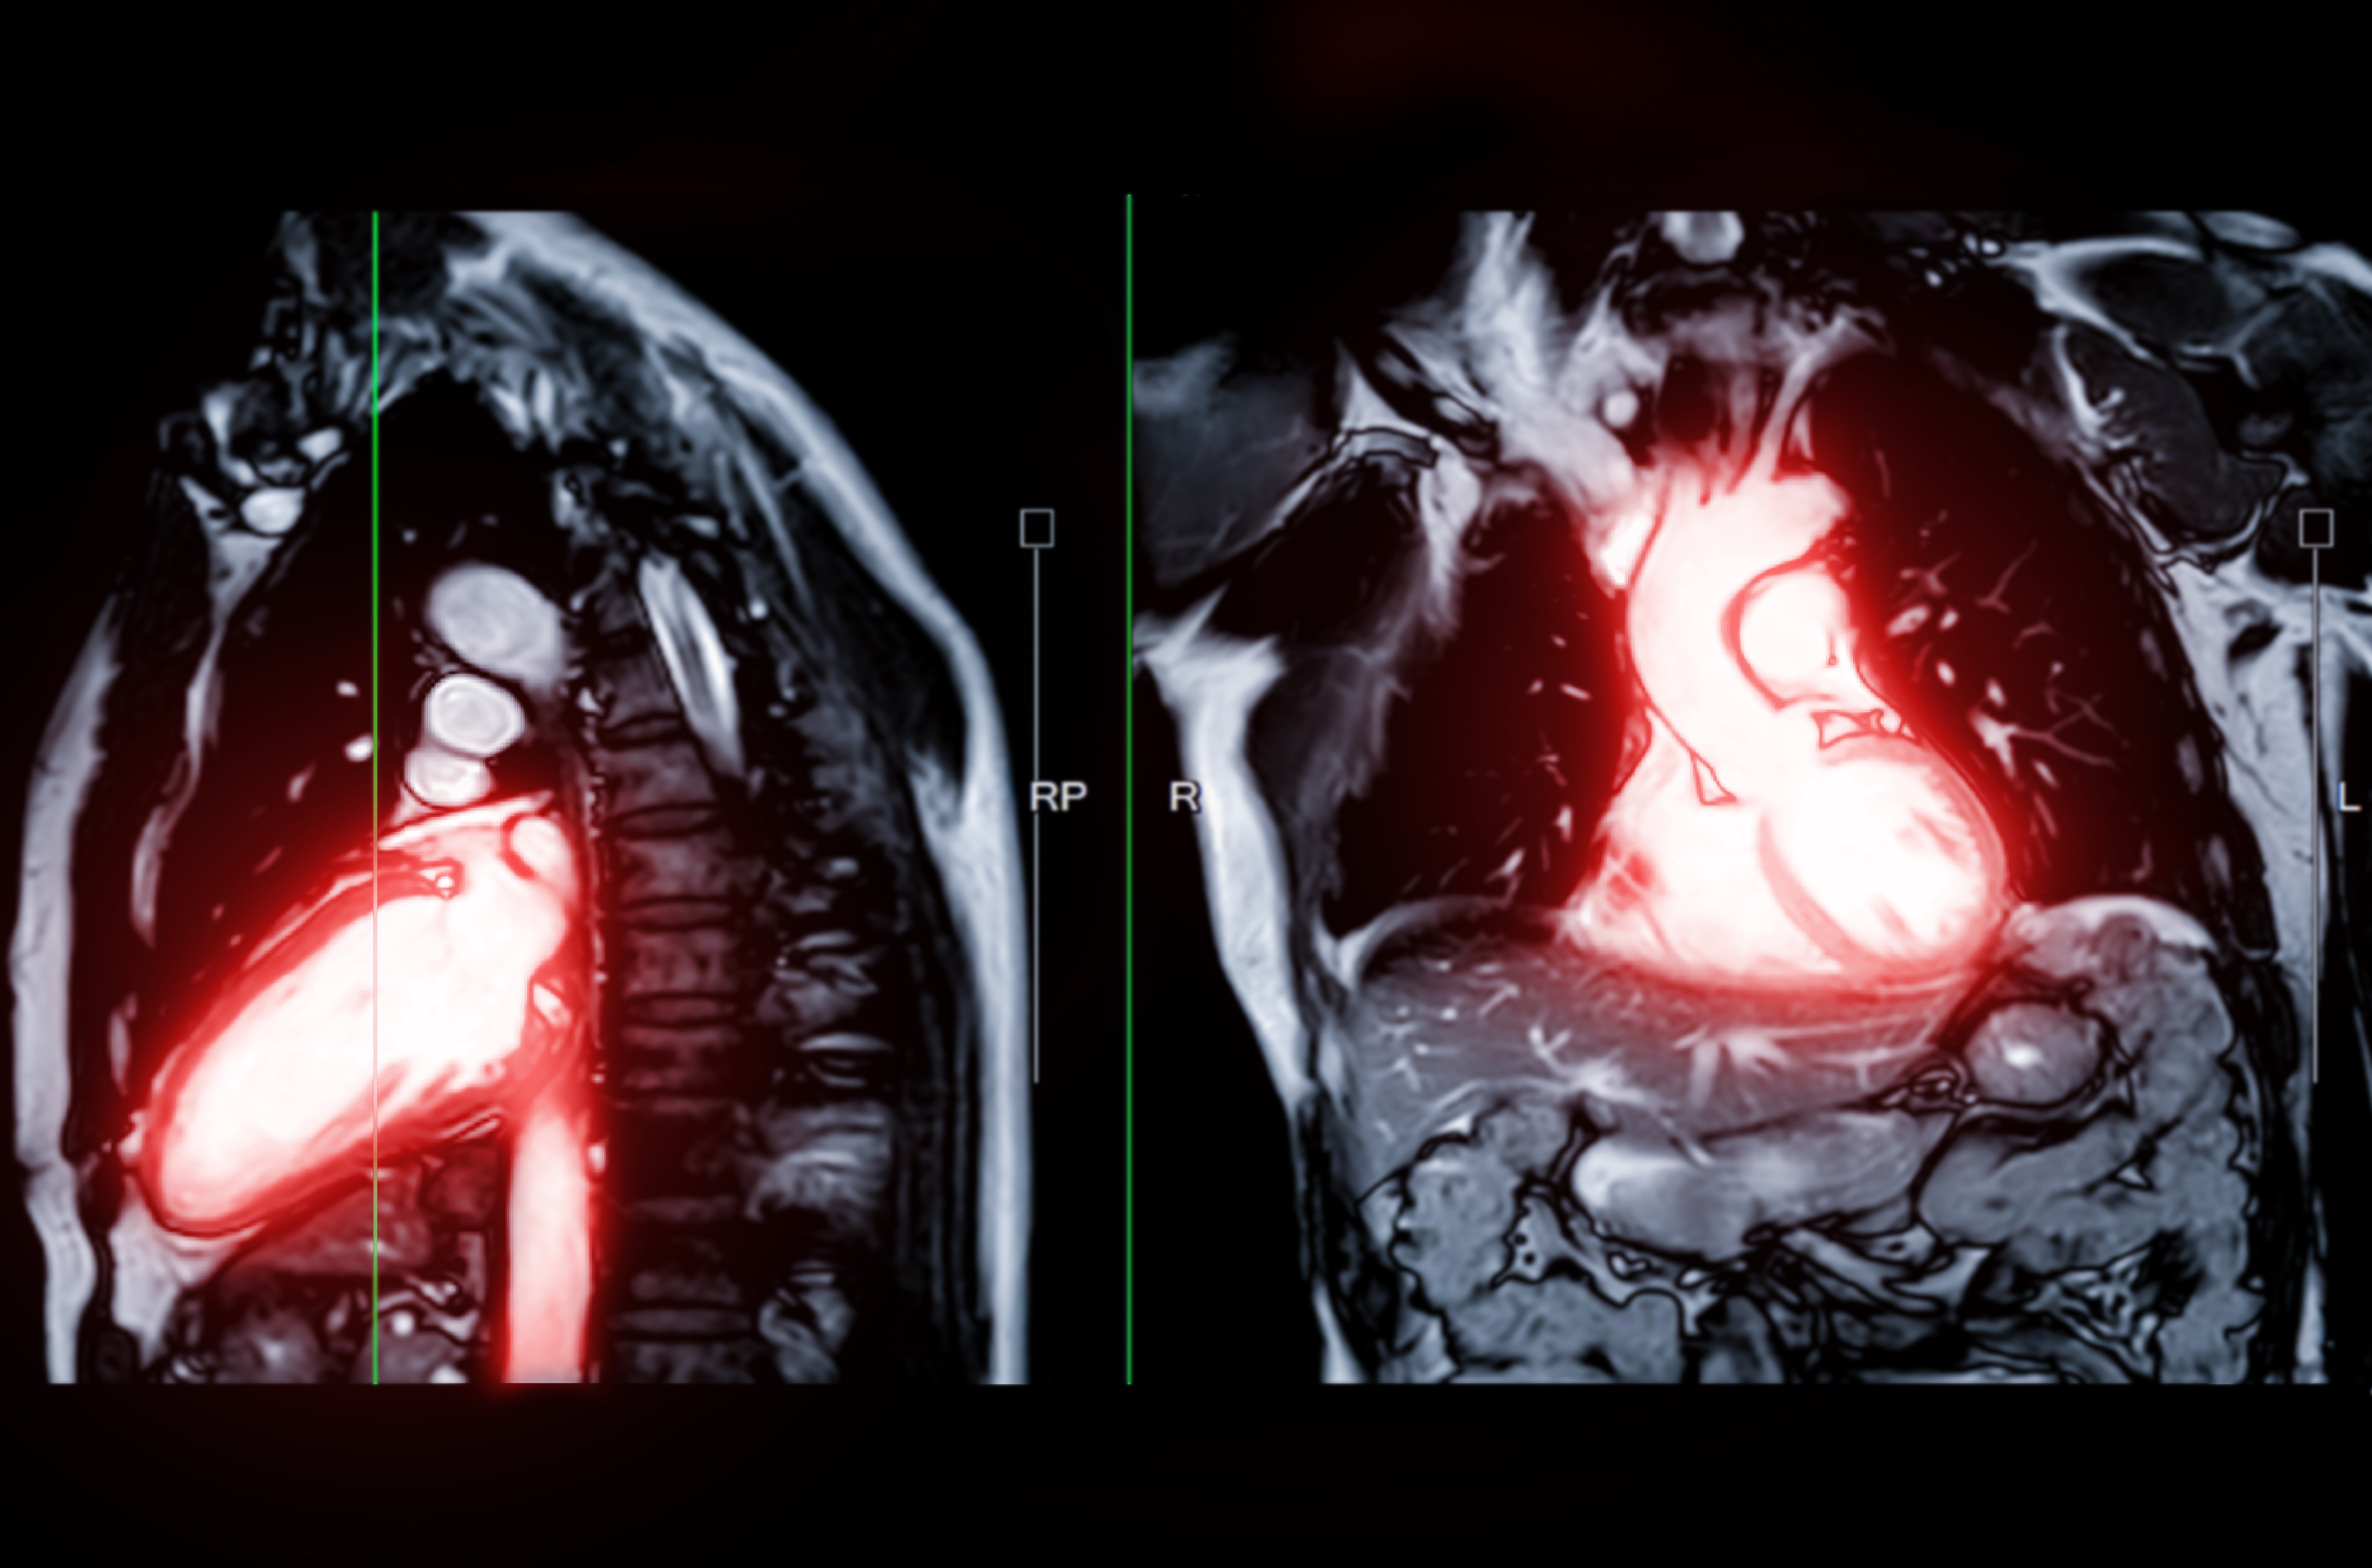

L'imagerie cardiovasculaire est une sous-spécialité de la radiologie qui permet de visualiser l'état circulatoire de l'appareil cardio-vasculaire à des fins diagnostiques, thérapeutiques ou de recherche. Elle permet d’analyser votre cœur et l'anatomie environnante.

Elle est utilisée pour diagnostiquer et gérer les maladies cardiaques, déterminer si une crise cardiaque s’est produite et l’étendue des dégâts, trouver la cause de certains symptômes tels que des douleurs thoraciques et un essoufflement, surveiller le cœur pour évaluer si les traitements fonctionnent.

L’imagerie cardiaque peut être utile pour diagnostiquer et gérer de nombreuses maladies cardiaques.

Les examens comprennent les radiographies, l’échographie, l’IRM et le scanner.